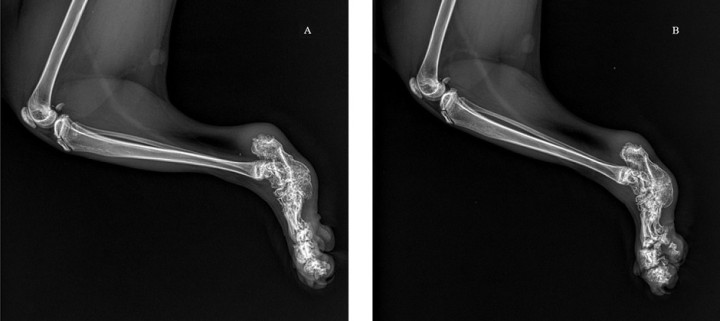

Ante la sospecha de una osteocondrodisplasia, está indicado realizar radiografías de la cola para valorar vértebras caudales, de los carpos, metacarpos y falanges, así como de los tarsos, metatarsos y falanges (Figs. 4 y 5). Estas mostraron acortamiento de vertebras coccígeas, así como de los huesos metacarpianos, metatarsianos y falanges, y deformación y degeneración articular a esos niveles.

<p>Proyección dorsoplantar de la parte distal de las extremidades posteriores (<em>pes</em>) del paciente donde se observa acortamiento, deformidad y engrosamiento de tarsos, metatarsos y falanges, así como pérdida de los espacios articulares de dichas zonas.</p>

Proyección dorsoplantar de la parte distal de las extremidades posteriores (pes) del paciente donde se observa acortamiento, deformidad y engrosamiento de tarsos, metatarsos y falanges, así como pérdida de los espacios articulares de dichas zonas.